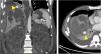

A contrast-enhanced CT scan showed a dense fluid area 25mm in diameter, suggestive of a haematoma, around the liver.

A dedicated CT scan of the liver showed new haematomas forming around the liver, and a 1.5cm pseudoaneurysm at the subdiaphragmatic surface of segment VII of the liver (Fig. 1).

A subsequent angiogram done via a right femoral approach confirmed the presence of this pseudoaneurysm which was being supplied by the superior branch of the right phrenic artery. Embolisation coils were placed in the pseudoaneurysm sac and in its feeding artery (Fig. 2).